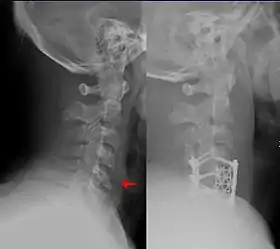

![]() این شکستگی در مهرههای گردنی تحتانی، یکی از شرایطی است که توسط جراحان اورتوپدی و جراحان مغز و اعصاب درمان میشود. | |